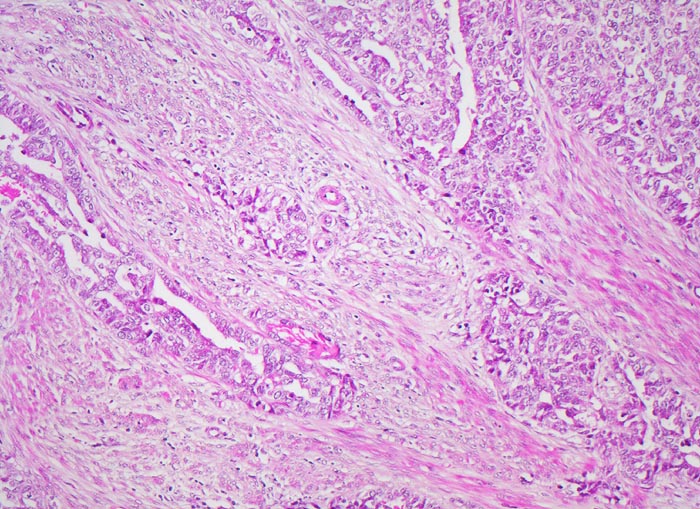

Endometrioide Karzinome bestehen aus tubulären Drüsen, welche von einem mehrreihigen Epithel ausgekleidet werden. Schleim ist meist nicht oder nur apikal in den Zellen vorhanden. Die Ausdehnung der soliden Areale und die zytologischen Atypien bestimmen den Differenzierungsgrad (low-grade versus high-grade). Metaplastisches Plattenepithel findet sich häufig in endometrioiden Karzinomen und hilft bei der Abgrenzung von anderen Subtypen. Das endometrioide Karzinom kann sich innerhalb von Adenomyoseherden im Myometrium entwickeln (> 4482). In diesen Fällen kann die Bestimmung der Infiltrationstiefe erschwert sein.

• Anstelle des Endometriums findet sich in der linken Hälfte des Uteruskavums ein Adenokarzinom bestehend aus architektonisch komplexen Drüsen. Die Drüsen liegen teils dos à dos ohne erkennbares Stroma zwischen zwei Drüsenschläuchen.

• Tumorzellverbände infiltrieren die glatte Muskulatur des Myometriums.

• Tumordrüsen ausgekleidet von mehrreihig angeordneten Tumorzellen mit hyperchromatischen polymorphen längsovalen Tumorzellkernen mit zahlreichen Mitosen. Die Morphologie der Tumordrüsen erinnert an proliferatives Endometrium.